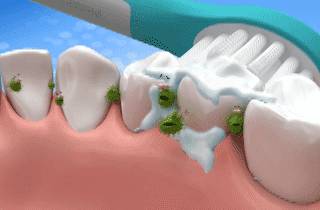

牙周炎引起牙松动,首要处理当然是完善的牙周基础治疗(去除根源),这包括大家熟知的洗牙和牙周深部刮治。这样就将位于牙龈上下的菌斑、牙石等刺激物清除干净,控制牙周组织炎症。

除此之外,小编觉得,每日刷牙和使用牙线是最省时、省钱、省事的护牙措施。当然,养成定期口腔检查的习惯,早预防早发现早治疗是最最好的呢!